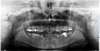

In the mandible, teeth 32, 33, 42, and 43 were impacted. The remaining teeth, except for third molars, showed severe dystrophy with advanced periodontitis and mobility (Fig. 1). Despite periodontal management, progressive tooth loss occurred. At 27 yr old, a conservative approach was no longer possible, and the mandibular teeth needed to be removed.

Fig. 1 Panoramic radiograph (October 2018) of Case 1 prior to dental extractions, showing generalized root and crown dysplasia. |